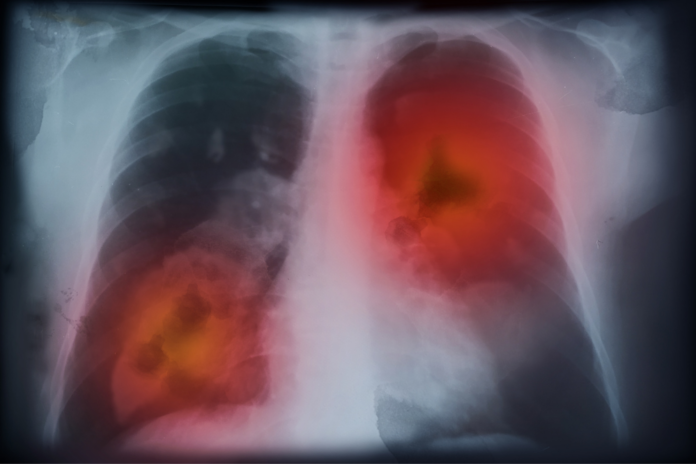

El cáncer de pulmón tiene cada vez mayor impacto en mujeres y se diagnostica cada vez en edades más tempranas, según el Grupo Español de Cáncer de Pulmón (GECP), que presento este jueves una radiografía de la situación de la patología en España, a partir de datos de 31.587 pacientes de toda España de su Registro de Tumores Torácicos

Se detecta un mayor impacto de la patología en mujeres, así como «cierto rejuvenecimiento en la edad al diagnóstico», que está detrás del «imparable crecimiento de este tumor», según el GECP, principal grupo de investigación clínica independiente de la patología, que cuenta con un Registro de Tumores Torácicos con datos clínicos de 31.587 pacientes procedentes de 89 centros hospitalarios de toda España.

En la mayoría de los casos se trata de cáncer de pulmón no microcítico (83,2%), seguido del cáncer de pulmón microcítico (14,2%). El 80% de los pacientes presenta la enfermedad en un estadio avanzado en el momento del diagnóstico (más del 52% en un estadio VI). Los principales síntomas al diagnóstico son tos, dolor, disnea y, en ocasiones pérdida de peso.